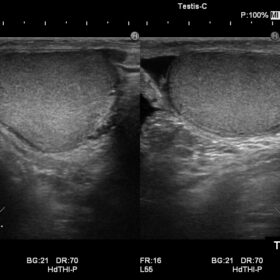

Ultrasound Noblus – Image Gallery and Videos

Using Hitachi’s own broadband technology to increase the harmonic frequency bandwidth, the High definition dynamic Tissue Harmonic Imaging (HdTHI) mode gives you both high resolution and excellent penetration. The HI Rez+ tissue adaptive filter optimises contrast resolution, border enhancement and noise suppression without reducing frame rate, and the HI Com, real-time spatial compounding technology, that uses multiple beams on transmit and receive, is especially beneficial for clarifying luminal structures